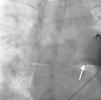

Case reportA 44-year-old man presented with several weeks of palpitations. He also described symptoms of dyspnea with mild exertion and substernal chest discomfort at rest. He had a history of long-standing systemic hypertension. The 12-lead ECG showed atrial fibrillation with rapid ventricular rate. His 2D Doppler echocardiogram revealed a mildly enlarged RA and right ventricle (RV). He subsequently underwent right and left heart catheterization with selective coronary angiography. Right and left heart catheterization with a full oximetry run to calculate shunts revealed Qp/Qs of 1.3. Selective coronary angiography was performed using right radial artery access, and showed no significant coronary disease. However, angiography of the aortic arch showed a single trunk takeoff for the large vessels from the aortic arch (Figure 1). Using right femoral vein access, a 5-Fr multipurpose diagnostic catheter was advanced into the upper (Figure 2) and middle (Figure 3) right pulmonary veins as they opened into the superior vena cava (SVC). To exclude any possible associated atrial septal defect, an MP-1 catheter was engaged into what proved to be a coronary-cameral fistula (CCF) opening into the RA separately from the coronary sinus (Figure 4), the CCF went from the coronary vein to the RA and the coronary sinus was also filled with contrast retrogradely from the vein (Figure 4). Pulmonary angiography using a 5-Fr pigtail catheter showed a moderately dilated pulmonary trunk (Figure 5). Following consultations with the cardiothoracic surgery and pediatric cardiology teams, it was felt that the best course of management would be to follow the patient clinically with serial echocardiography, as there was no significant right-to-left shunt.

SS is a complex form of PAPVR, which is a connection failure between the right pulmonary veins and the LA during fetal development. Variations in PAPVR include the right pulmonary veins draining into the SVC-LA junction, RA, or IVC, or as in our case, separately to a high SVC. In SS, an anomalous right pulmonary vein generally draining the entire right lung but occasionally the middle and superior lobes, may descend in a cephalad-to-caudal direction toward the diaphragm with a crescent (scimitar) shape. This vein then curves sharply to the left just above or below the IVC-RA junction.8 The anomalous right pulmonary venous trunk usually courses anterior to the hilum of the right lung and connects to the IVC just superior to the orifices of the hepatic veins. Rarely, it drains into the left atrium, with normal venous return.9

In this patient, the right upper and middle pulmonary veins drained into the high SVC and then ultimately into the RA, leading to increased pulmonary circulation as shown by the enlarged right chambers and main pulmonary artery.